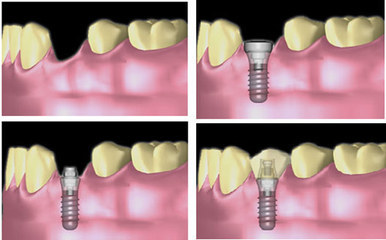

种牙流程图

种牙流程图牙种植护理影响牙种植价格